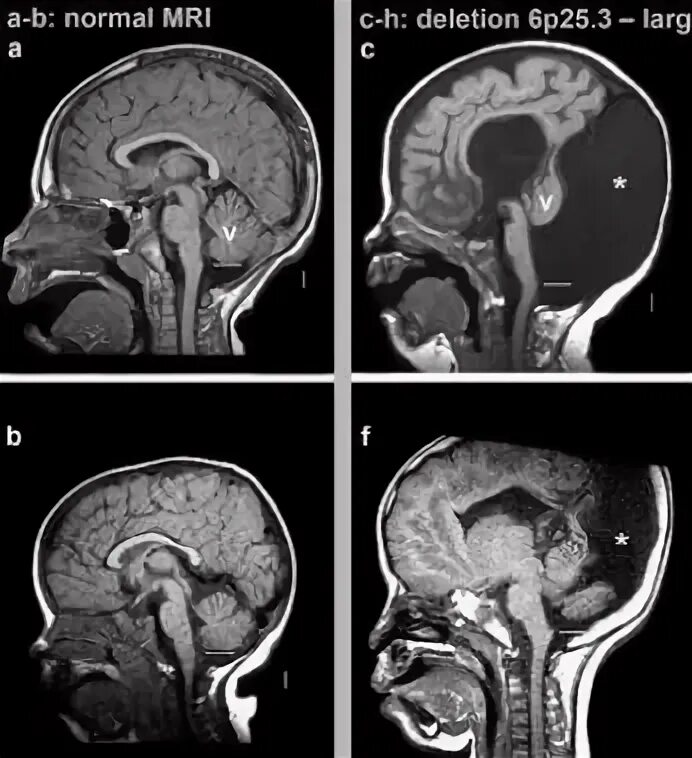

Денди уокера мрт